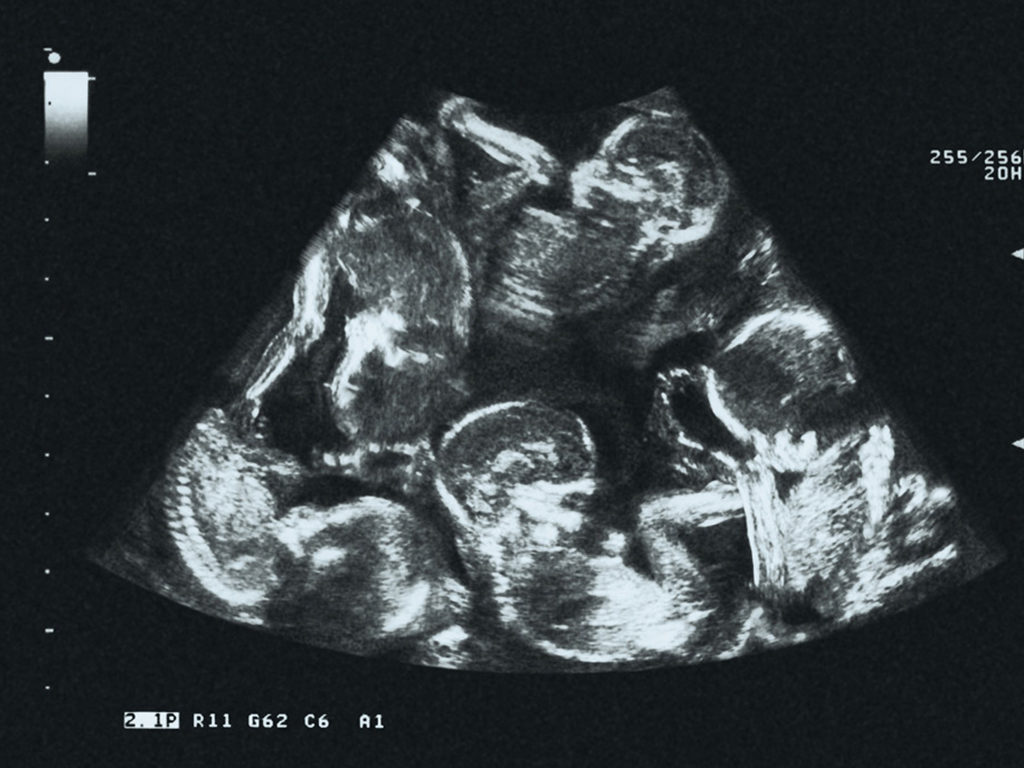

The couple already knew they were having four babies. But this time the ultrasound showed that there was a fifth baby in utero. Kinova was having quintuplets. But why hadn’t doctors detected it before?